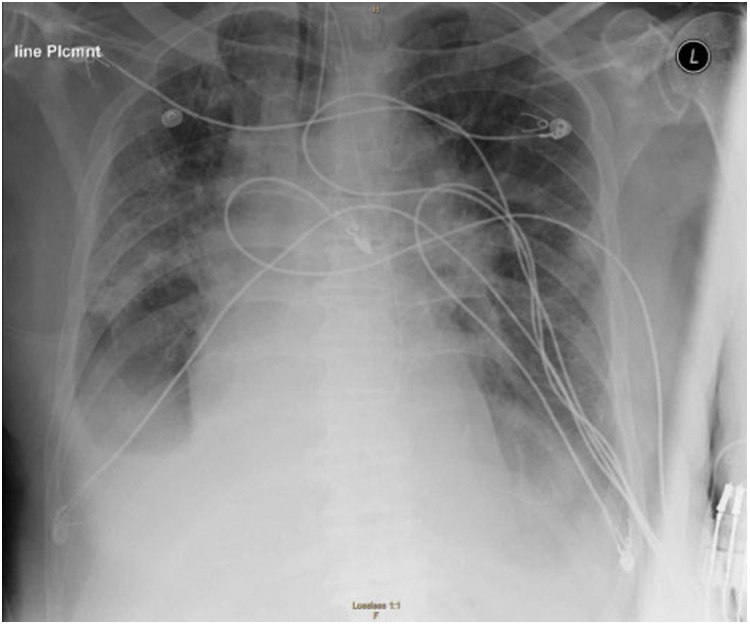

It can be noted that the performance of the previously mentioned methods is satisfactory; however, practically, a significant amount of background noise (such as skeleton, lines, shoulder, etc.) is usually contained in the images of the original CXR as depicted in Fig. 1. Consequently, the sensitivity of classifiers can be reduced significantly. Although some models have reached state-of-the-art performance, the background features were most likely employed for feature learning. On the other hand, although training the machine learning models with a high number of background noises may yield better results, these noises will result in significant interference with the recognition impact, practically.

Figure 1: Original CXR image